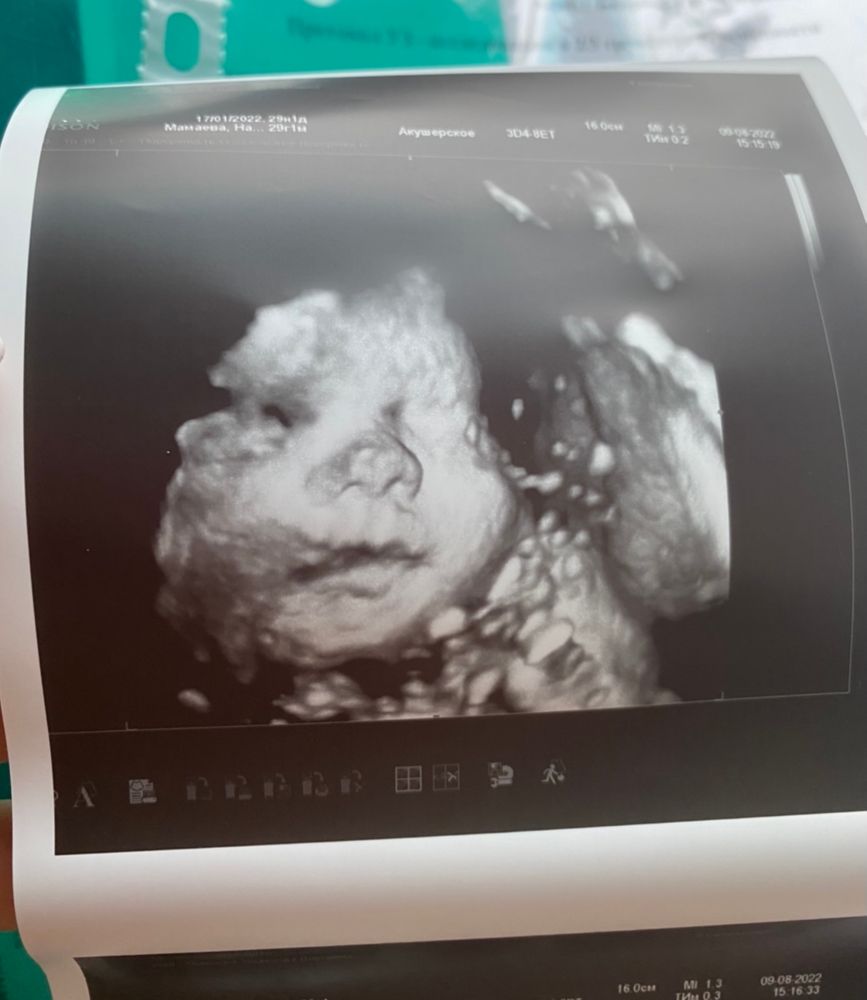

Мы сделали на 29 неделе, считаю, самый оптимальный срок, они уже хорошо сформированы, с пухлыми щечками, все же на 22 рановато.

16.08.2022